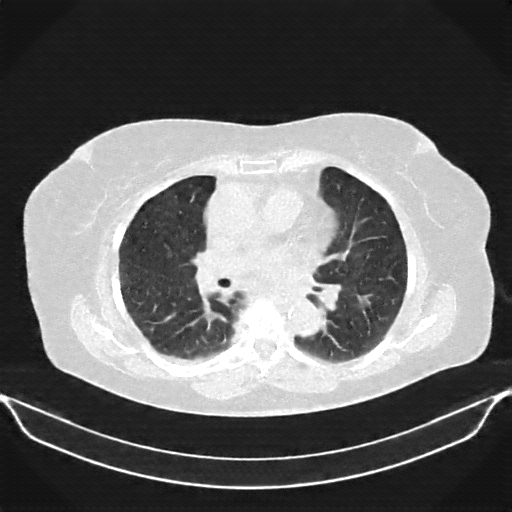

Original NATIVE CT scan (input)

Lung window (WL -600, WW 1500 β†’ Low βˆ’1350, High +150)

Actual HU range: [-1024.0, 150.0]